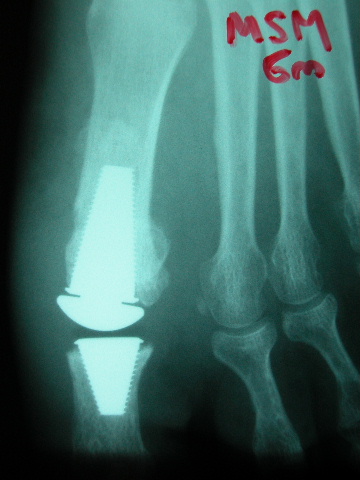

ACT Prótesis de hallux en artrosis.

ACT Prótesis de hallux. Perfil.